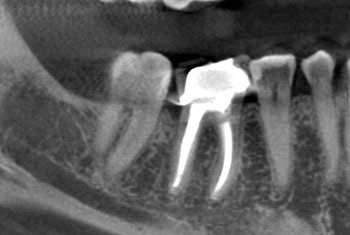

Case 1:A J-shaped lesion

As dentists, we can become desensitized to how important each tooth is to a patient and how impactful we can be in saving one. This patient’s dentist told her that #30 had a vertical root fracture and she needed to have it extracted and replaced with a dental implant. No other treatment options were given. She came independently for a second opinion and said how devastating it would be for her to lose a tooth.

Tooth #30 had a diagnosis of previous root canal treatment with symptomatic apical periodontitis. The mesial root had a classic J-shaped radiographic lesion and a narrow probing defect from the buccal furcation to the root apex. No crack could be seen on what little root surface was visible. The likelihood of VRF, or the possibility of a failing root canal with a chronic apical abscess, were discussed. The latter could be treatable. The plan was to attempt re-treatment after internal inspection for a possible VRF.

Fig. 1: Preoperative PA.

Fig. 2: Postoperative PA.

Fig. 3: Recall PA.